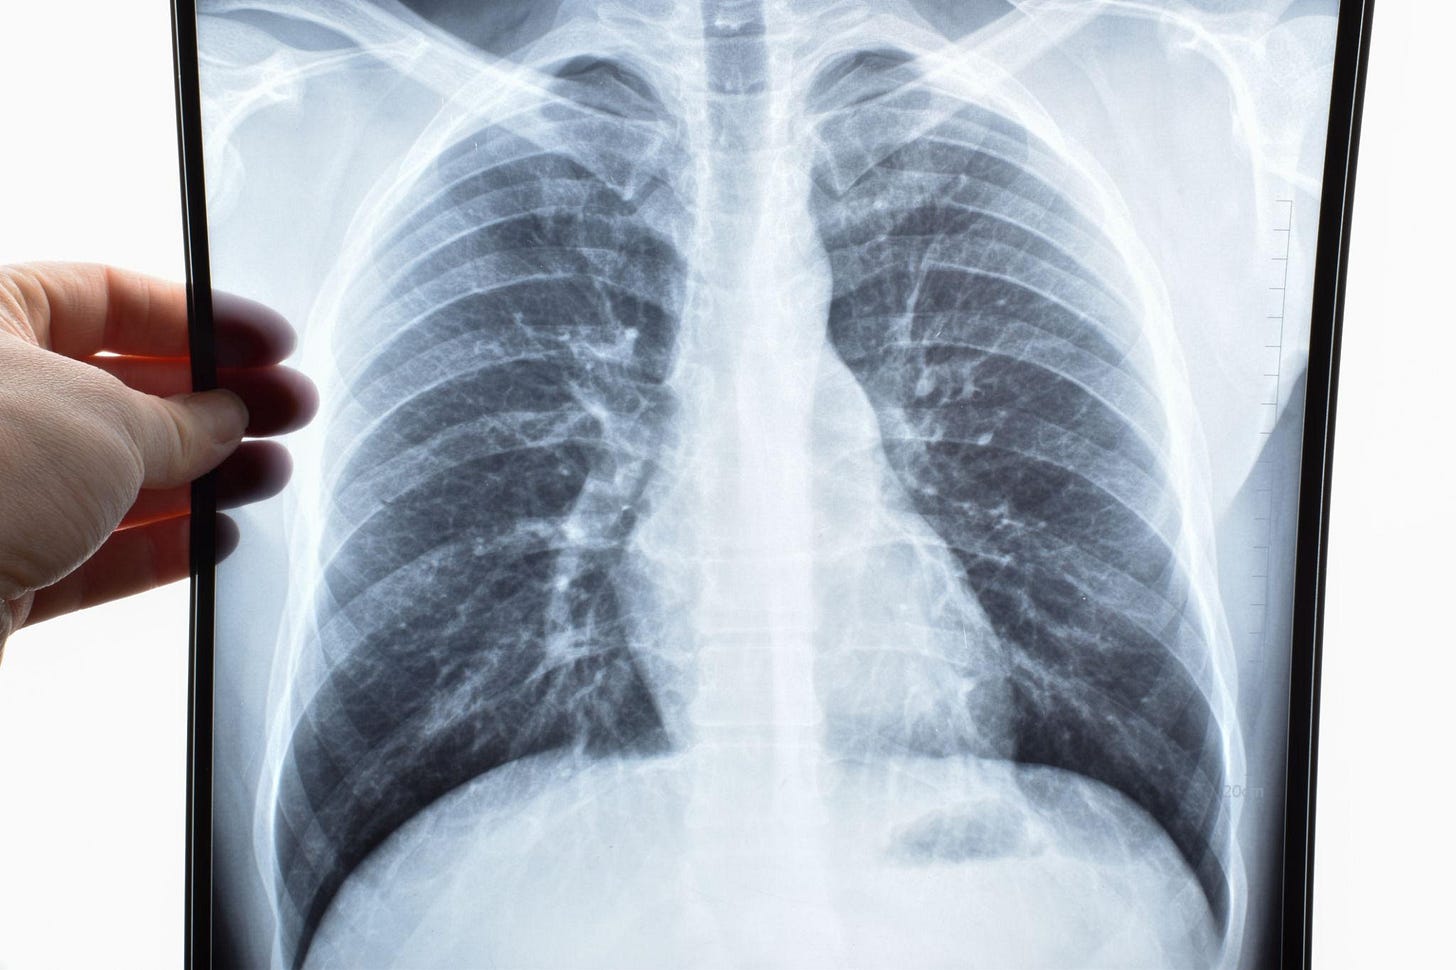

Mesothelioma and Asbestos Exposure

Asbestos was widely used for decades in construction materials, insulation, and industrial products due to its heat-resistant properties. Exposure—often occupational or secondary—has been linked to mesothelioma, lung cancer, and other serious pulmonary diseases such as asbestosis. These diseases typically develop years or decades after exposure, making diagnosis and causation complex. Although asbestos litigation is a mature area of law, it remains highly active, with new claims filed regularly. Recent cases increasingly involve asbestos-contaminated consumer products, including talc. Courts across the country continue to see significant verdicts and settlements in favor of individuals suffering from these devastating illnesses.